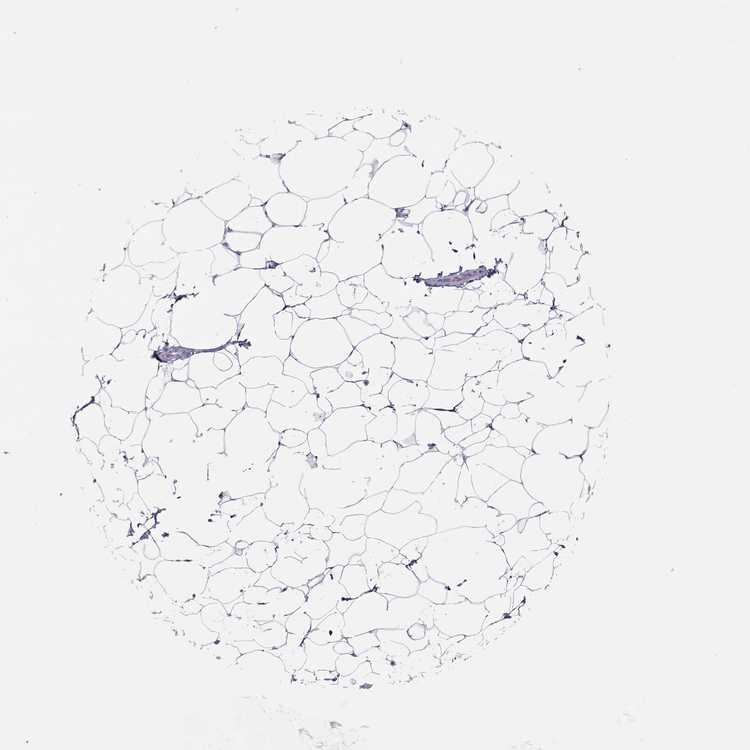

TISSUE PRIMARY DATA BREAST Show tissue menu

BREAST - Antibody stainingi

Antibody staining in the annotated cell types in the current human tissue is reported as not detected, low, medium, or high, based on conventional immunohistochemistry profiling in selected tissues. This score is based on the combination of the staining intensity and fraction of stained cells.

Each image is clickable and will lead to virtual microscopy that enables deeper exploration of all samples and also displays staining intensity scores, fraction scores and subcellular localization as well as patient and tissue information for each sample.

Antibody HPA076123Antibody HPA077266

Adipocytes Not detectedNot detected

Glandular cells LowNot detected

Myoepithelial cells Not detectedNot detected